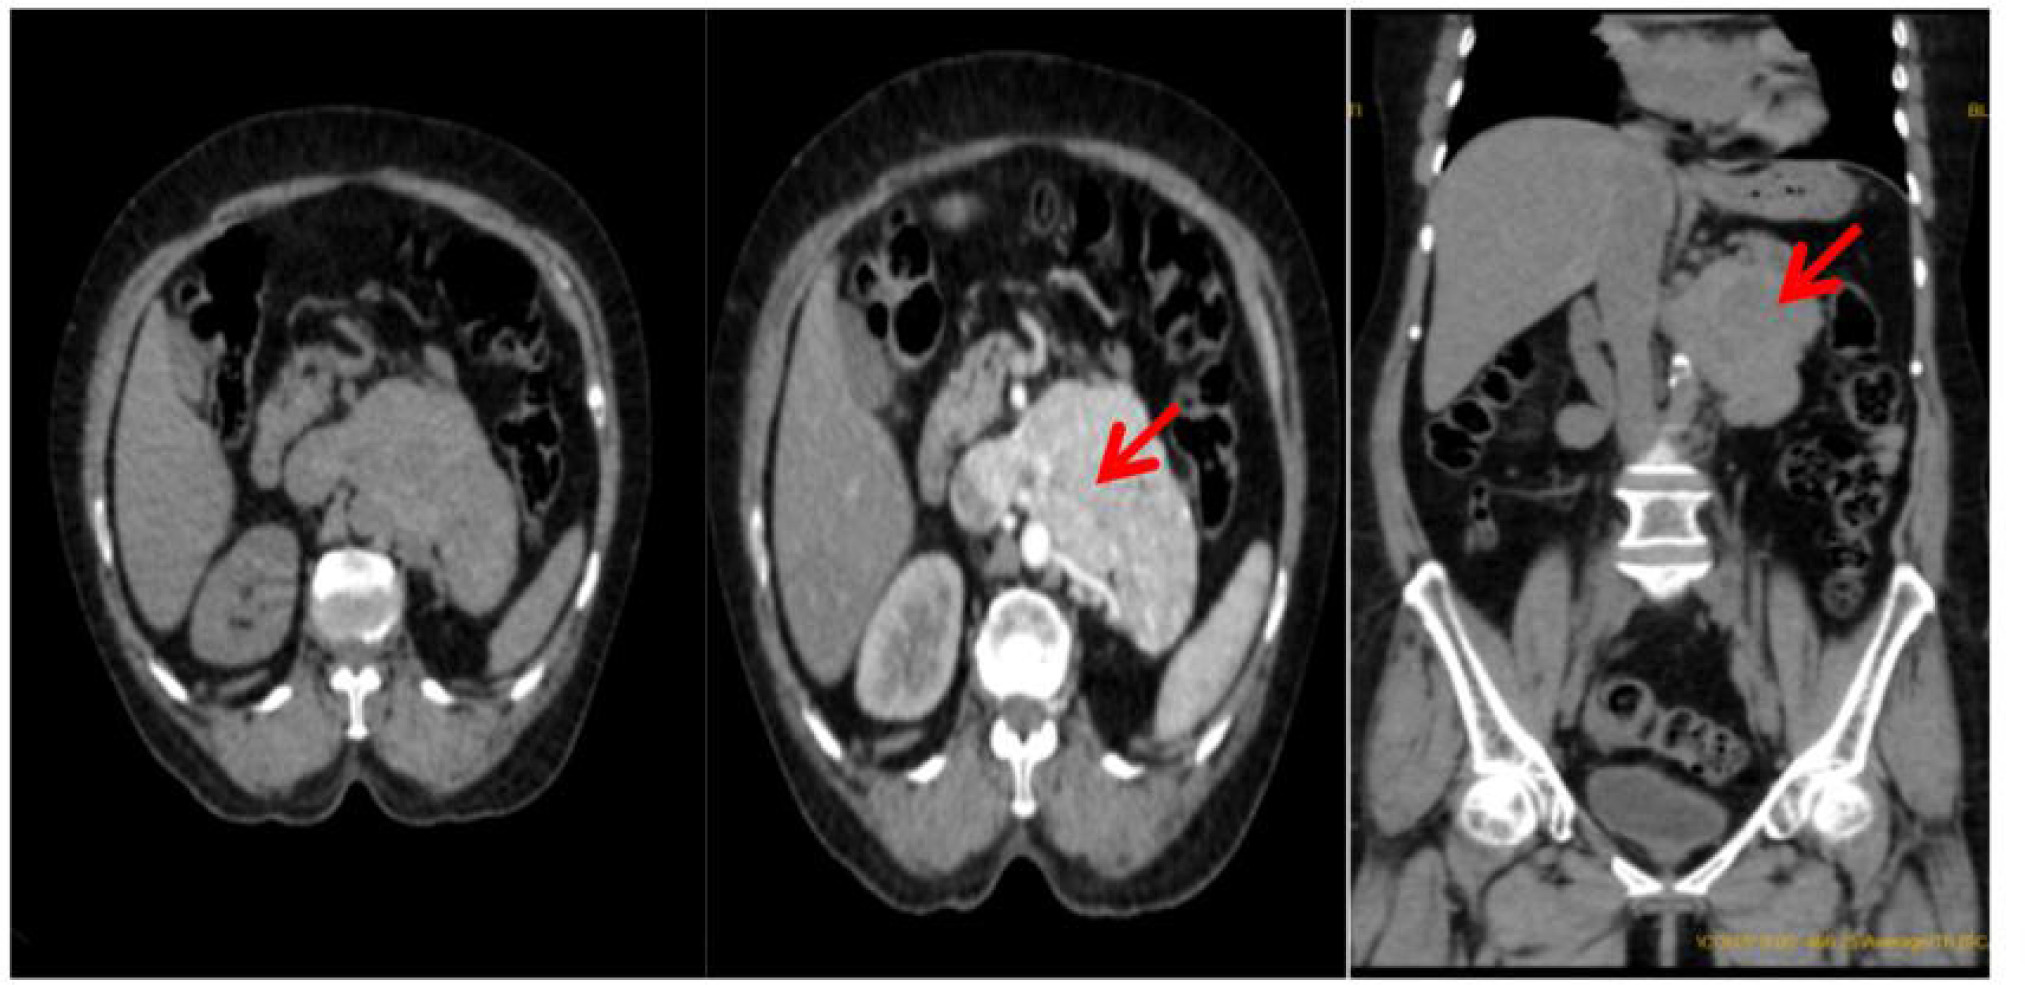

A contrast-enhanced CT urogram was then performed, which revealed a heterogeneously enhancing left retroperitoneal mass with necrotic areas. The mass had extended into the periaortic region and involved the IVC, suggestive of recurrent RCC with possible vascular invasion (Figure 2).

Figure 2: Contrast CT showing heterogeneously enhancing mass in the left retroperitoneum with intrinsic foci of necrotic areas with involvement of periaortic lesion and extension into the inferior vena cava.

Based on the findings of recurrent metastatic RCC with associated cutaneous vasculitis, the patient was started on Sunitinib 50 mg daily as neo-adjuvant therapy. Sunitinib is a tyrosine kinase inhibitor commonly used in the treatment of RCC, and it was chosen because of its efficacy in both treating RCC and managing PV. After starting the treatment, the patient showed significant improvement. The cutaneous lesions began to resolve, with a marked reduction in the size and pain associated with the lesions. Imaging studies also demonstrated a decrease in the size of the retroperitoneal mass, indicating a favorable response to therapy (Figure 5).

Figure 5: The complete resolution of the cutaneous lesions with regression in the tumor size after treatment with sunitinib.